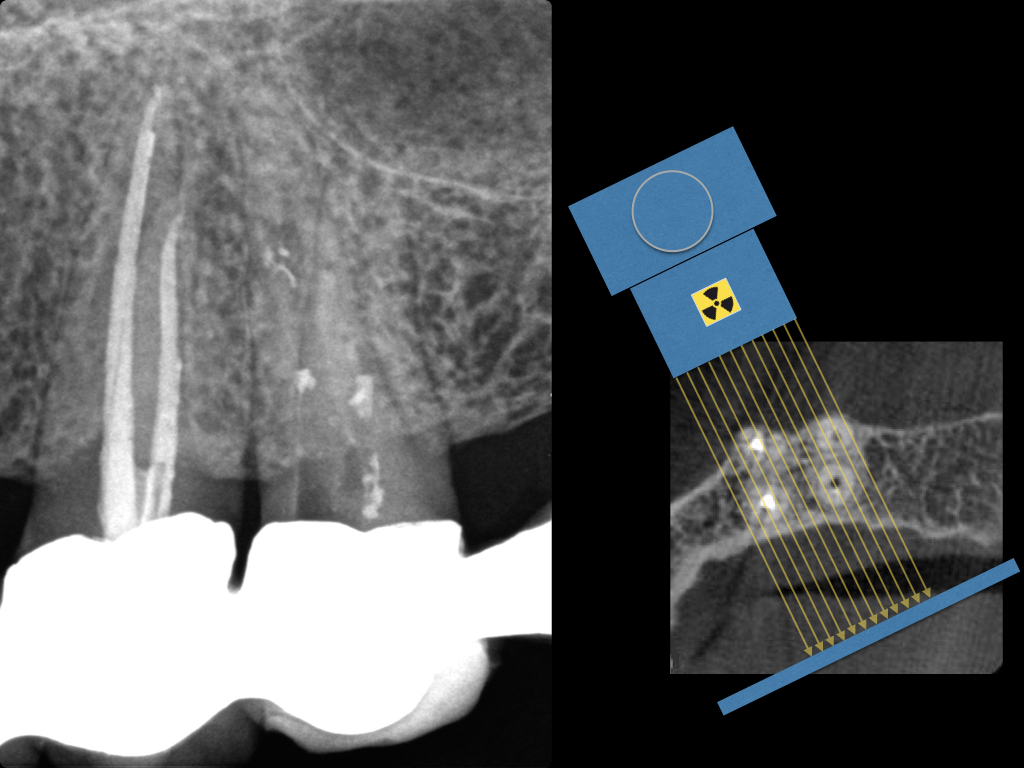

Es ist zu sehen … (2)